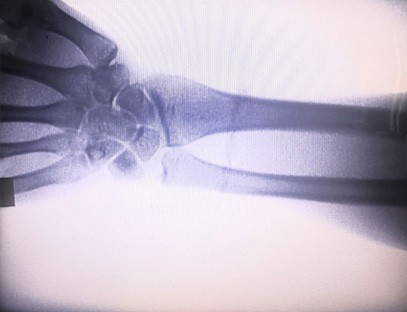

Hình ảnh tức thời di độngMáy chụp X-quanglà một thiết bị y tế được thiết kế riêng cho các phòng khám chỉnh hình để thực hiện chụp X-quang các chi. Thiết bị này sử dụng khả năng xuyên thấu của tia X và sự khác biệt về mức độ hấp thụ tia X giữa các mô khác nhau trong cơ thể con người để chuyển đổi thông tin cấu trúc bên trong thành hình ảnh trực quan, do đó hỗ trợ bác sĩ trong chẩn đoán và điều trị. Đặc biệt phù hợp cho các phòng khám tư nhân, bác sĩ thú y và bệnh viện thú cưng. Máy chụp X-quang chi được sử dụng trong thú y để hỗ trợ bác sĩ thú y trong chẩn đoán và điều trị bệnh.

Chuyên môn:Được thiết kế cho nhu cầu của các phòng khám chỉnh hình, đặc biệt phù hợp choChụp X-quangcủa các chi như bàn tay, cổ tay, khuỷu tay, vai, đầu gối, mắt cá chân, v.v.

Hình ảnh rõ nét:Công nghệ hình ảnh kỹ thuật số tiên tiến được sử dụng để cung cấp hình ảnh X-quang chất lượng cao, giúp bác sĩ chẩn đoán tình trạng bệnh chính xác.